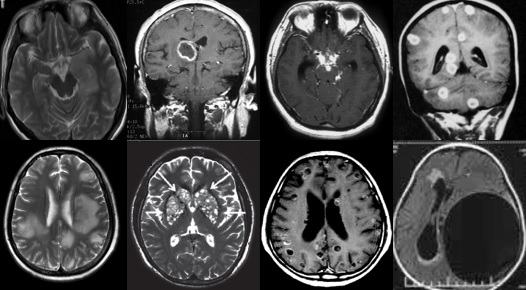

重要申明:以下每个部分会配磁共振图片,因疾病和影像之间存在同病异象、同像异病,为避免误导,图片不标注疾病,请各自鉴赏,另其中有部分图片来源于网络,有疑问可与本人联系。

N--neoplasm,肿瘤

各种肿瘤,如胶质瘤、淋巴瘤、脑膜瘤、血管内淋巴瘤,生殖细胞瘤、各种转移瘤、心房粘液瘤等。神经纤维瘤病也可在中枢出现影像学上类似脱髓鞘的病变。

I--infection,感染

指的是各种感染,病毒(单纯疱疹病毒、带状疱疹…)、细菌(革兰阳性、革兰阴性、球菌、杆菌…)、结核、。真菌、梅毒、各种寄生虫(囊虫、弓形虫、吸虫、裂头蚴等)。还有进行性多灶性白质脑病(PML)、CJD、Whipple’s 病等。亚急性细菌性心内膜炎。